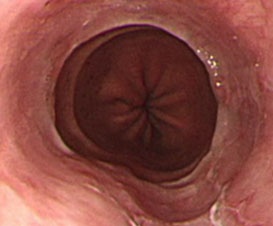

위염은 현대인의 생활습관과 밀접한 관련이 있는 질환으로, 주로 스트레스와 불규칙한 식습관이 주요 원인으로 작용합니다. 위염은 위점막에 염증이 생기는 것으로, 급성위염과 만성위염으로 나뉘며, 각기 다른 원인과 증상을 보입니다.

급성위염은 세균이나 바이러스 감염, 혹은 약물에 의해 급격히 발생하며, 만성위염은 오랜 기간 동안의 자극과 염증으로 인해 위점막이 위축되는 상태를 말합니다. 이러한 만성위염은 헬리코박터 파일로리균 감염이 주요 원인 중 하나입니다.